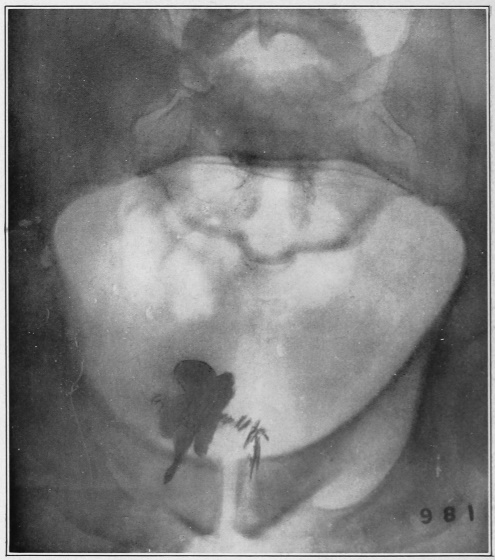

Nine Radiograph Illustrations Showing Mucus Channels and Cavities200

CHAPTER V.

Rebellion of our outraged Internal Economy.

The small intestine is that portion of the alimentary canal which begins at the stomach and ends at the large intestine. Its usual length is twenty feet. The diameter, which at the upper portion (duodenum) is two inches, gradually becomes less, until at the lower end it is but one inch.

Now, the length of the inner coat of this small intestine—the mucous membrane—is about double that of the intestine itself. Think of wearing a coat twice as long as yourself! How do you think this is accomplished in the case of the muscular tube under con­sid­er­ation? Well, Nature, having a most peculiar function to perform, has thrown this mucous coat or tube into a thousand folds (valvulæ conniventes, or “winking valves”). These folds form valves, occupying from one-third to one-half the circum­ference of the bowel. The greatest width of each fold is at the center, where it measures from a quarter to half an inch. Over this great expanse of mucous membrane we find studded ten million five hundred thousand intestinal villi, whose office it is to absorb the food substances in their passage through the canal.

Fig. 9.

Stomach, liver, small intestine, etc. (Flint.) 1, inferior surface of the liver; 2, round ligament of the liver; 3, gall-bladder; 4, superior surface of the right lobe of the liver; 5, diaphragm; 6, lower portion of the œsophagus; 7, stomach; 8, gastro-hepatic omentum; 9, spleen; 10, gastro-splenic omentum; 11, duodenum; 12, 12, small intestine; 13, cæcum; 14, appendix vermiformis; 15, 15, transverse colon; 16, sigmoid flexure of the colon; 17, urinary bladder.

Those that have observed the anatomical illustrations of the small intestines must have been struck by their apparently inextricably tangled convolutions. In life, these convolutions are constantly changing their locations, as though they were a mass of worms.

Fig. 10.

The cæcum, dorso-mesial view, showing the ileum-side of the ileo-cæcal valve, and the beginning of the three muscular ribbons. (Gerrish.)